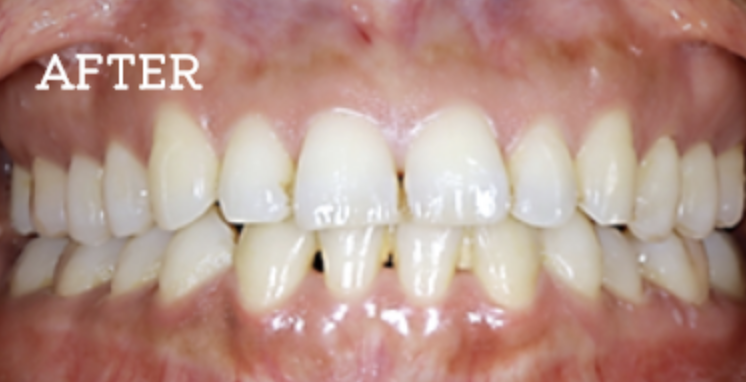

症例

お困りごとを参考に、治療のbefore・afterが確認できます。治療過程や期間、費用などを参考にご覧ください。